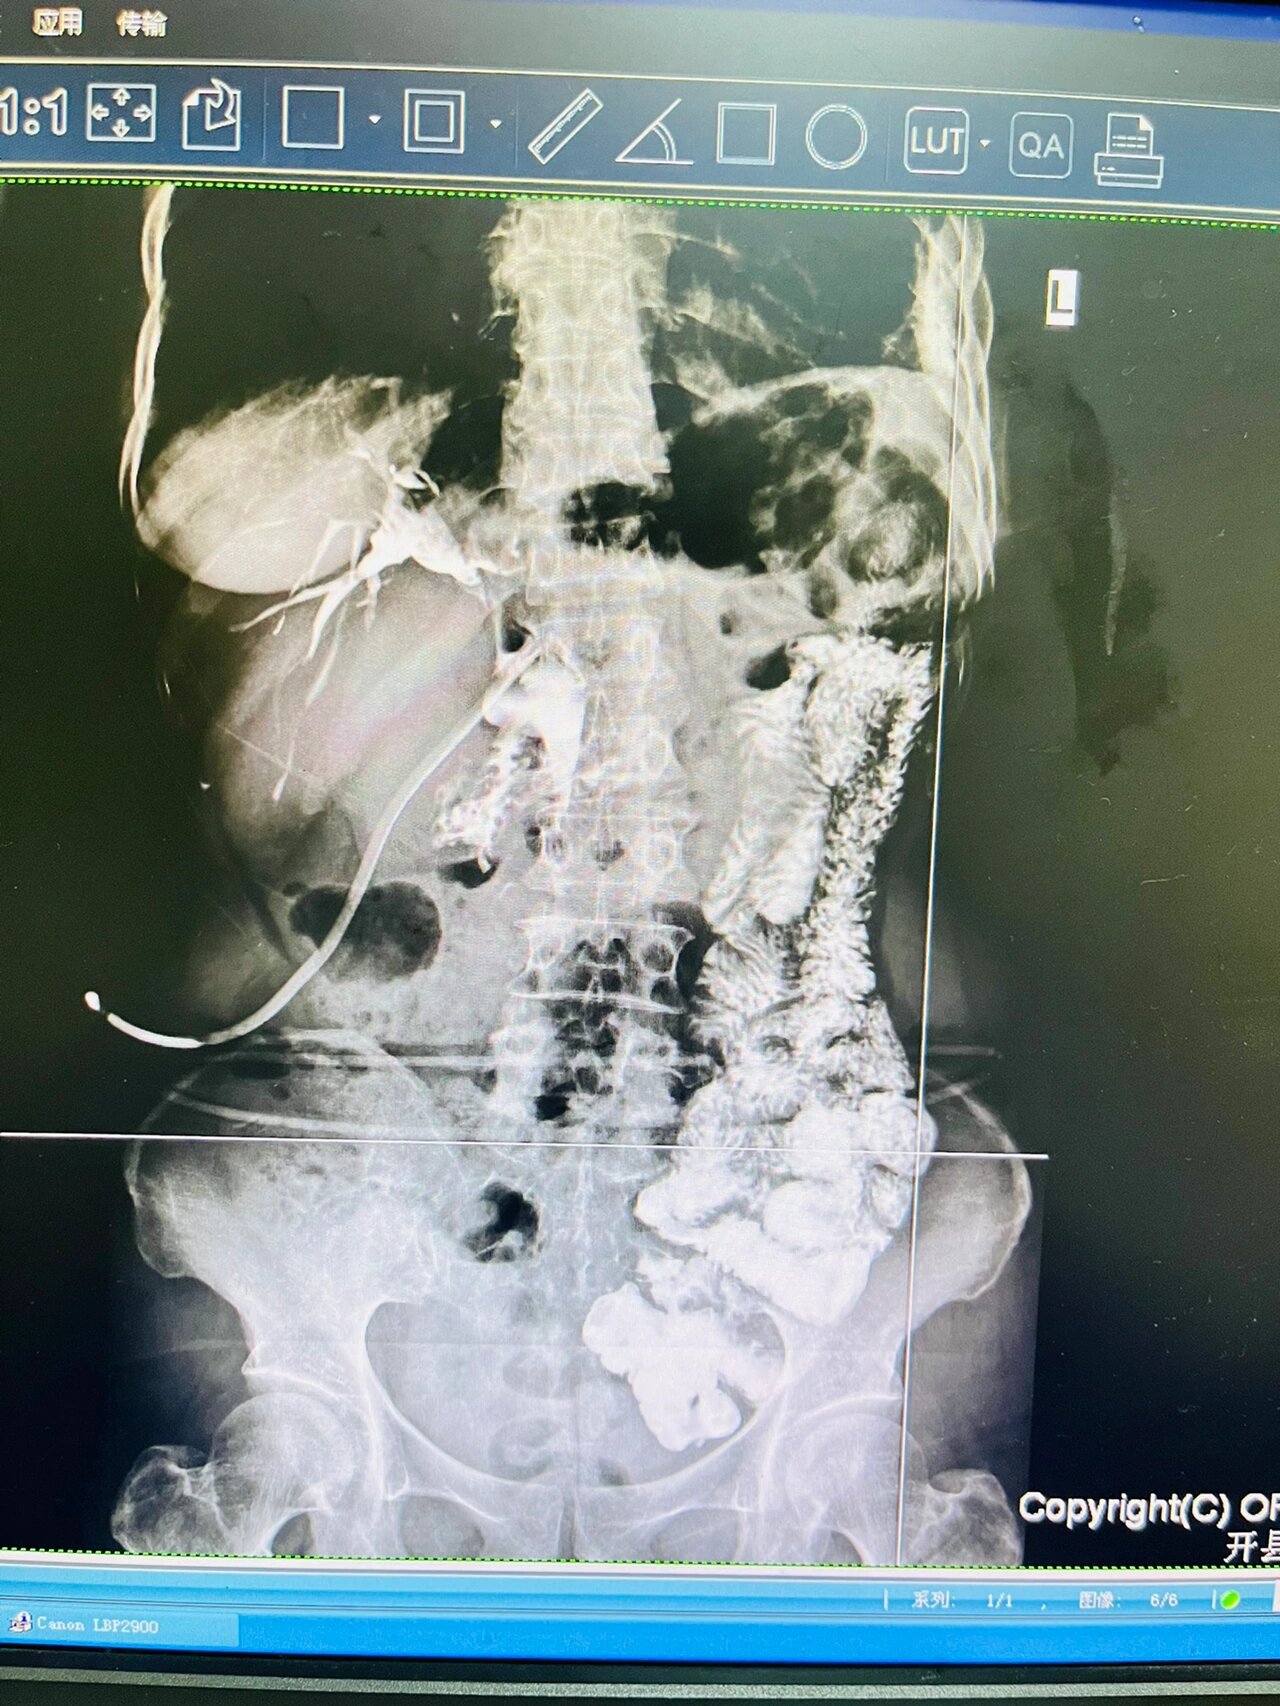

术后t管造影 未见明显结石残留

t管引流术后造影片子,求助诊断结果